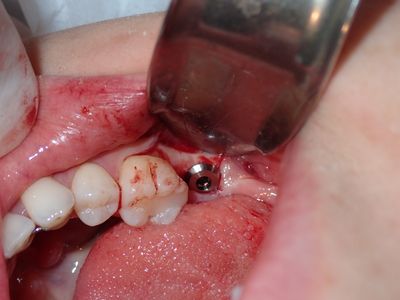

JYeung - 47 implant

Soft bone, some repositioning required due to distal slant of anterior tooth roots. Good end positioning